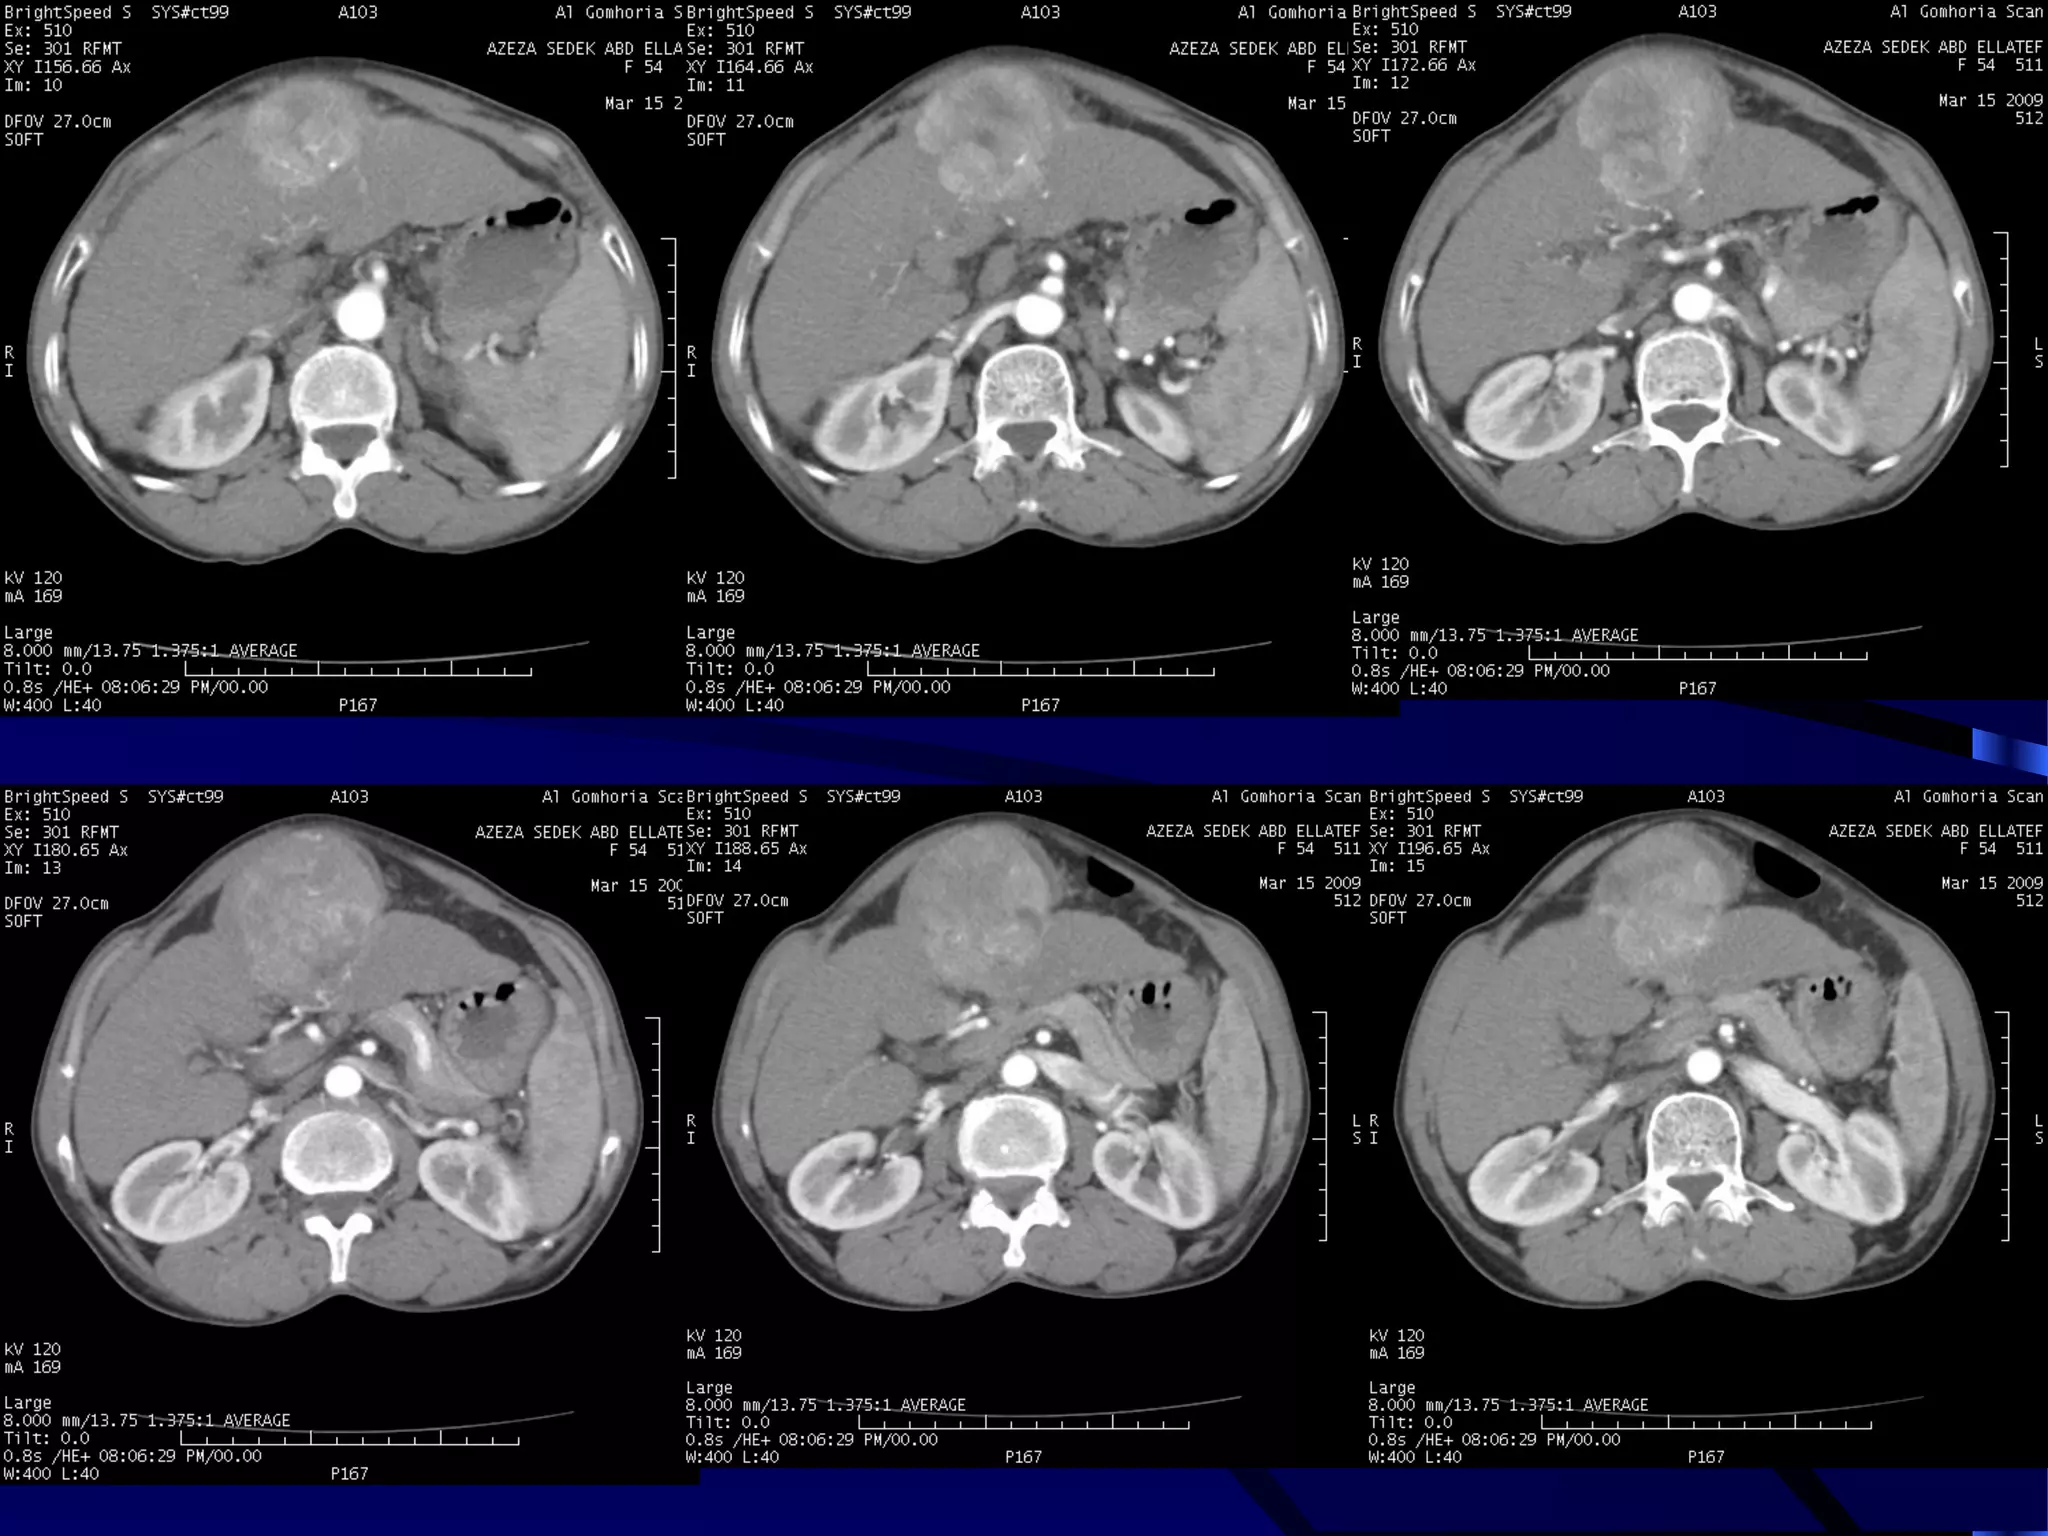

CASE (2)

OBSTRUCTED INFECTED KIDNEY

ENLARGED LEFT KIDNEY WITH MARKED STRANDING OF THE

PERINEPHRIC FAT AND OBSTRUCTING PELVIC CALCULUS

DOUBLE DENSITY VR IMAGE SHOWING

THE OBSTRUCTING CALCULUS